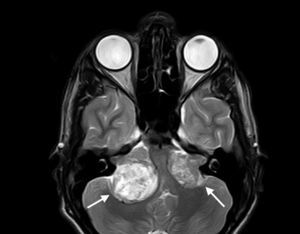

Neurological ManifestationsThe most widely-known characteristic of NF2 is the development of bilateral vestibular schwannomas (Figure 1).3 The presence of such lesions leads to diagnosis of the disease in the majority of cases and is considered a strong enough criterion for diagnosis (Table 1). These tumors appear in 95% of the patients and cause neurosensory deafness that presents at 27 years of age on average.2 Hearing loss is present in 95% of patients (although only two-thirds are aware of this) and does not depend on tumor diameter but rather the degree of nerve compression. In most patients with NF2, this is the first sign of the process.2 In the most serious cases, however, NF2symptoms present at a younger age and usually with less recognizable clinical manifestations, such as the onset of tumors at other sites, onset of neurological symptoms, and presence of skin or ocular lesions.1,4 One example of this is the appearance of schwannomas in other nerves of the body. Approximately 60% of those affected by NF2 have schwannomas in nerves other than cranial nerve 8,6 with the trigeminal nerve the second most frequently involved cranial nerve (29% of patients).2,5 These tumors can also be formed in other anatomical areas such as the spine. This occurs in 90% of patients with the disease, although only 30% of them have symptoms.5,6